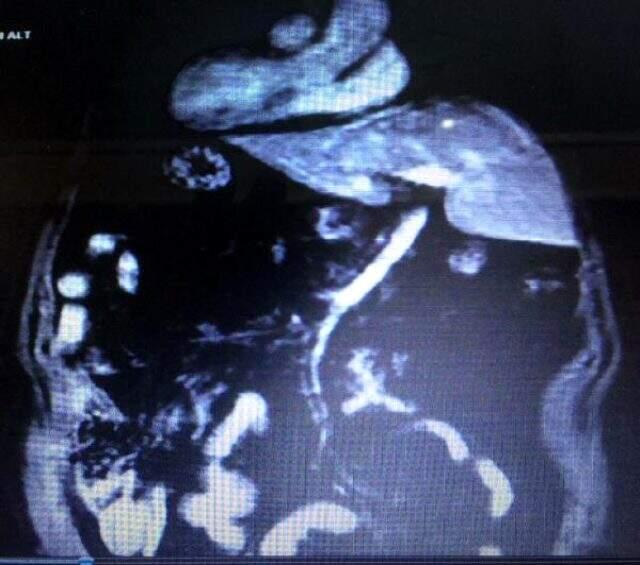

Alaşehir’de otobüs sürücülüğü yapan Şükrü Karacan, geçen 6 Ocak’ta karın ağrısı şikayetiyle Alaşehir Devlet Hastanesi Genel Cerrah Polikliniği’ne başvurdu. Genel Cerrahi Uzmanı Dr. Güvenç Diner tarafından muayene edilen ve gerekli analizleri yapılıp, röntgen sinemaları çekilen Karacan’a safra kesesinde taş olduğu teşhisi konuldu. Lakin, muayene de hekimleri şaşırtan şey Karacan’ın iç organlarının yerinin öteki insanlara nazaran karşıt yerde olması oldu. Genel Cerrah Diner, durumu hastasına anlattı. Büyük şaşkınlık yaşayan Karacan, “Kalbimin sağda olduğunu askerde öğrenmiştim ancak öbür organlarımın da aksi yerde olduğunu yeni öğrendim. Hekimimin sıhhatim açısından bir sakıncası olmadığını söylemesi beni rahatlattı” dedi.

Karacan’ın safra kesesindeki taşlar, ameliyatla alınıp, sıhhatine kavuşması sağlandı. Alaşehir Devlet Hastanesi Genel Cerrah Uzmanı Dr. Güvenç Diner, “Karın ağrısı şikayetiyle gelen hastanın ameliyatı için yaptığımız tetkikler sonucu iç organlarının aykırı yerlerde olduğunu fark ettik. Karaciğer olağan yerleşimi yeri olan sağda değil, solda olduğu için biz bu ameliyatı özellikli ameliyatlar sınıfına soktuk ve hastamız hastanemizde kolesistektomi operasyonu yaptık. Karaciğer ve safranın solda olması, bizim açımızdan ender görülen ve ameliyat tekniğimizin rutini dışında olan bir durumdu. Lakin, buna karşın ameliyatı yapıp, hastamızı sıhhatine kavuşturup, taburcu ettiğimiz için mutluyuz” dedi.

Alaşehir Devlet Hastanesi Başhekimi Opr. Dr. Kadir Gem de ameliyatın muvaffakiyet bir halde hastanelerinde yapılabilmesinin kendileri açısından gurur verici bir durum olduğunu söyledi. Ameliyatla sıhhatine kavuşan Şükrü Karacan’ın iç organlarından safra kesesi ve karaciğer olağanda sağda olması gerekirken solda; kalp ve dalağı olağanda solda olması gerekirken, sağda bulunuyor.